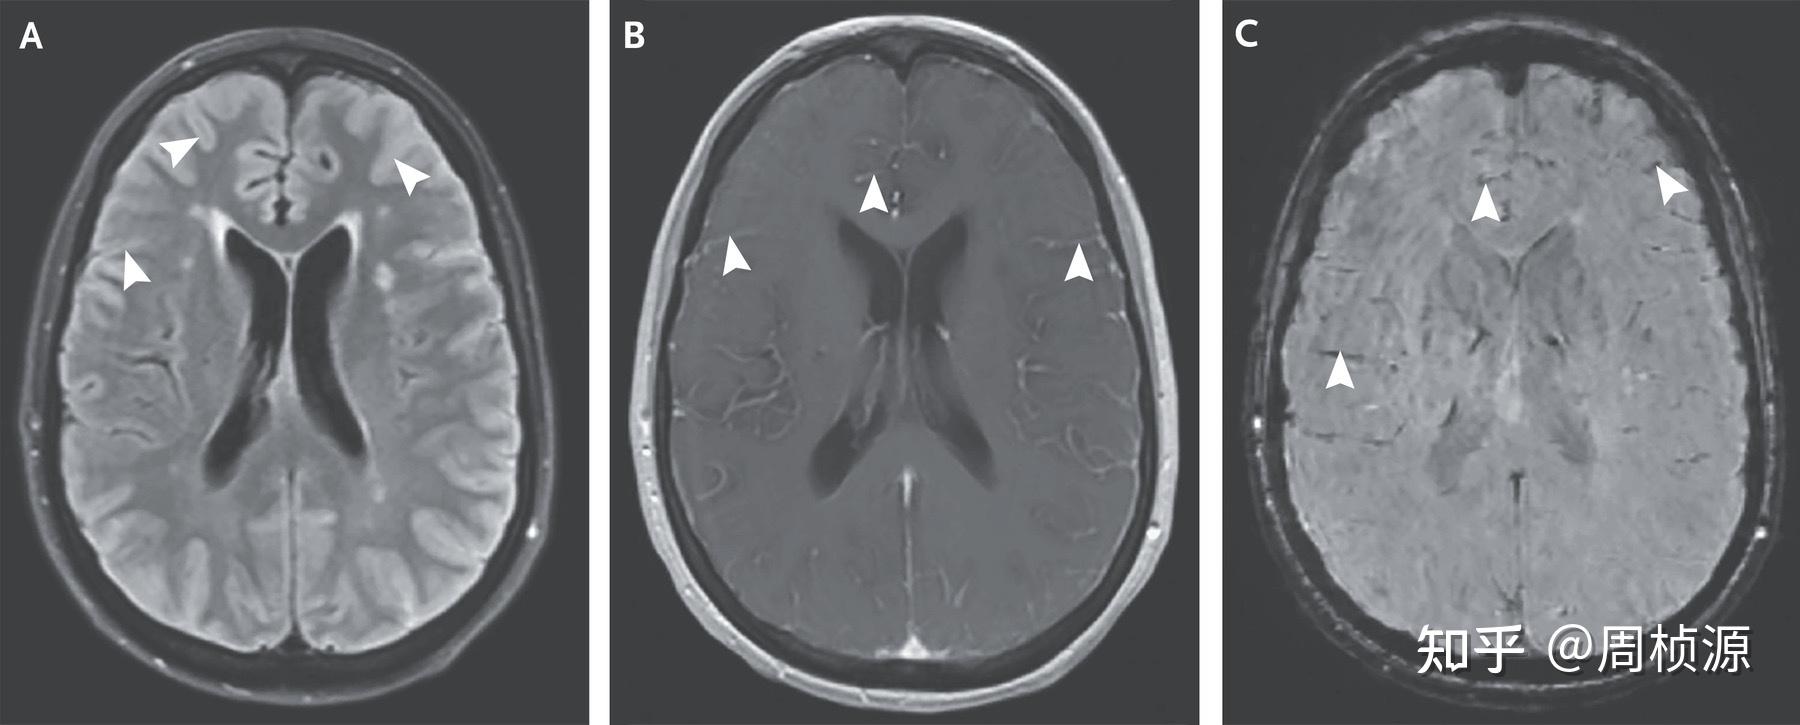

Nejm 2021 Case 22 知乎 Nejm Case Report 2021 presentation of case. presentation of case. Authors pavan k bendapudi 1 , michael j whalen 1 ,. presentation of case. sep 26, 2024. presentation of case. Nejm Case Report 2021.